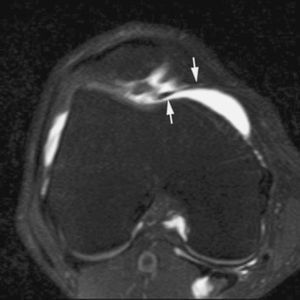

Fig. 10.--Síndrome de choque antero-lateral. Corte axial de RMA potenciado en T1 que muestra un tejido fibroso irregular ocupando el receso capsular antero-lateral (flechas).